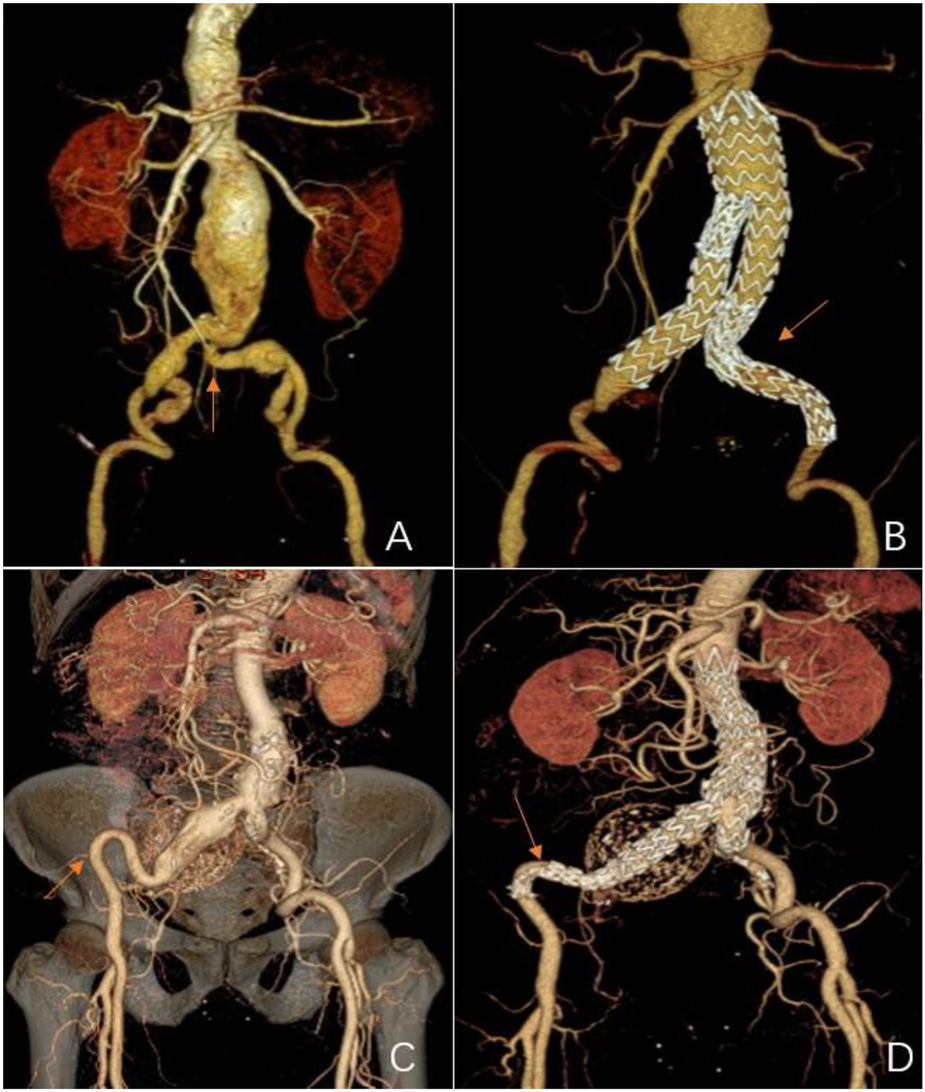

According to a pre-operative CTA, 157 patients suffered from severe tortuosity in the CIA or the EIA, and 50 of them were implanted with a BMS (Figure 1). Table 2 contains BMS-related data. With 66% vs. 44%, p = 0.05, the stent insertion rate in the EIA was higher in the BMS individuals than in the non-BMS individuals. In the BMS group, crossed-limb procedures accounted for 8%; in the non-BMS cohort, they accounted for 12% (p ≤ 0.05). The technical success rates for both cohorts were 100% (Table 3). The LGO was 2.0% (1/50) in the BMS cohort and 15% (17/107) in the non-BMS cohort (p < 0.05) (Table 3, Figure 2). Most limb occlusions transpired 6 months post-operation (Figure 3), with an overall LGO rate of 11.5% (18/157) in the entire cohort.

Figure 1

Representations of metal bare stents placed in the common or external iliac arteries. (A) and (C) Pre-operative 3D CT scans showing severe tortuosity of the left CIA (red arrow), and the double iliac sign of the right EIA (red arrow). (B) A post-operative 3D CT scan 18 months after EVAR of a bare metal stent that was placed in the left CIA (red arrow,) showing stent patency. (D) A post-operative 3D CT scan 124 months after an EVAR of the other bare metal stent that was placed in the right EIA (red arrow) showing stent patency.

The pre-operative CT images were selected to assess the anatomical features of the IA rather than angiography (Figure 1). Oshin et al. (15) elaborated that completion angiography is a two-dimensional representation of a three-dimensional (3D) object. This angiography is inadequate for determining limbs at risk for occlusion (12). CT can perform 3D reconstruction to overcome the shortcomings of angiography.